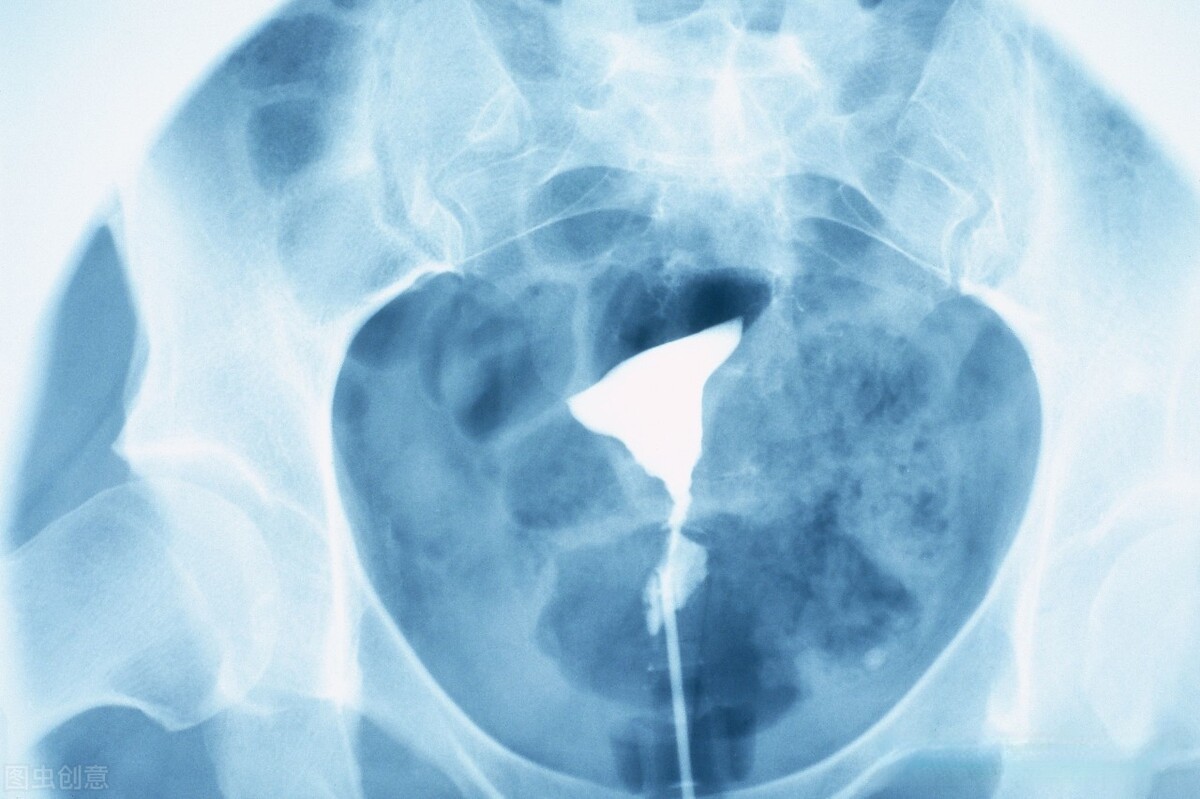

输卵管因素

输卵管发生异常阻止蝌蚪与卵子见面等原因导致不孕症。

输卵管炎:输卵管炎症容易引起伞端的粘连,或者管腔的阻塞等

输卵管位置异常:例如输卵管上举,输卵管粘连在盆腔壁上等会影响输卵管伞端拾卵。

输卵管病变:主要是就是输卵管堵塞,输卵管通而不畅等可能组织蝌蚪和卵子相遇影响怀孕

其次就是检测卵泡发育情况,可以从月经的3天左右开始连续的检测卵泡直到试孕。如果还是不怀孕。可以进行子宫输卵管造影检查,检查输卵管的情况。